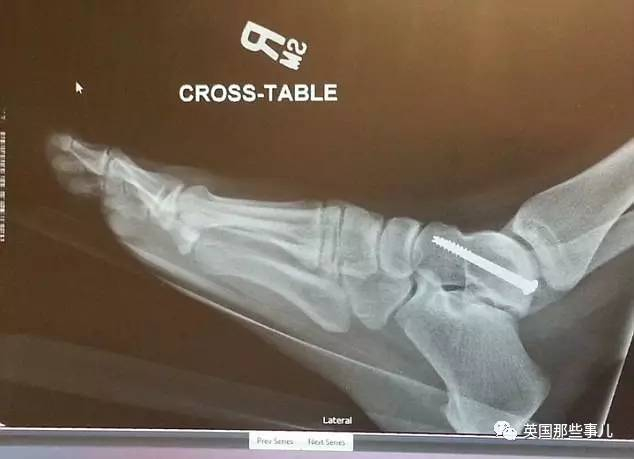

出院时,由于多处骨折,她的脚踝、臀部、膝盖上分别被打上了2个钢钉……